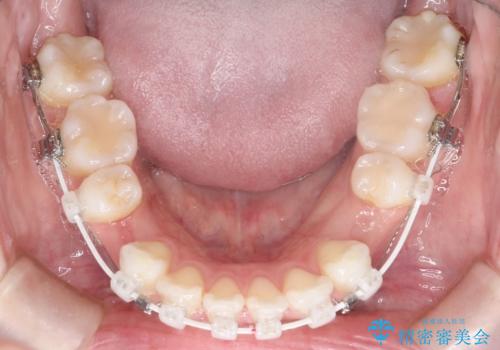

- 審美装置

- 2年1ヶ月

上下左右の歯を1本ずつ抜歯して、そのスペースを利用して口元を引っ込める計画としました。